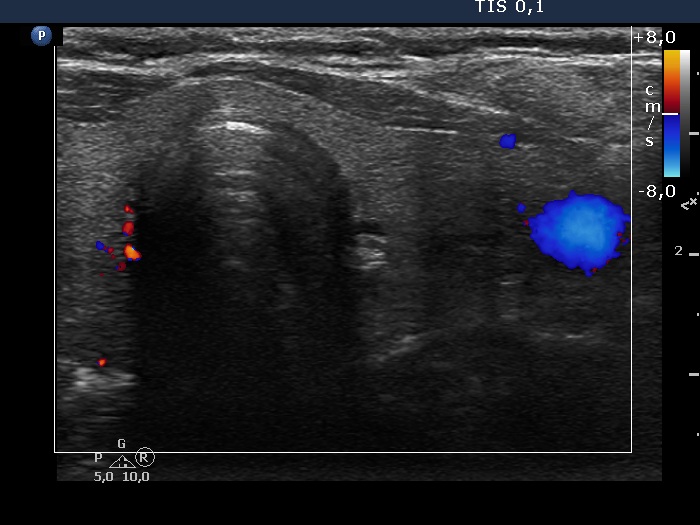

Intranodular hyperechogenic figures - case 372 (ultrasonographic picture 8)

Left lobe, trasnverse scan, color Doppler mode.